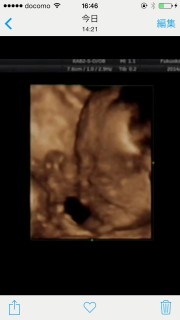

いつもカメラ目線男の子可愛い♡ 体重1017g?ちょっと頭が大きいって言われた7㎝…体も標準の中で大きいってお腹周り21㎝心配するほどではないって言われたけど… やっぱちょっと心配次また会えるのが楽しみです。(o^^o)